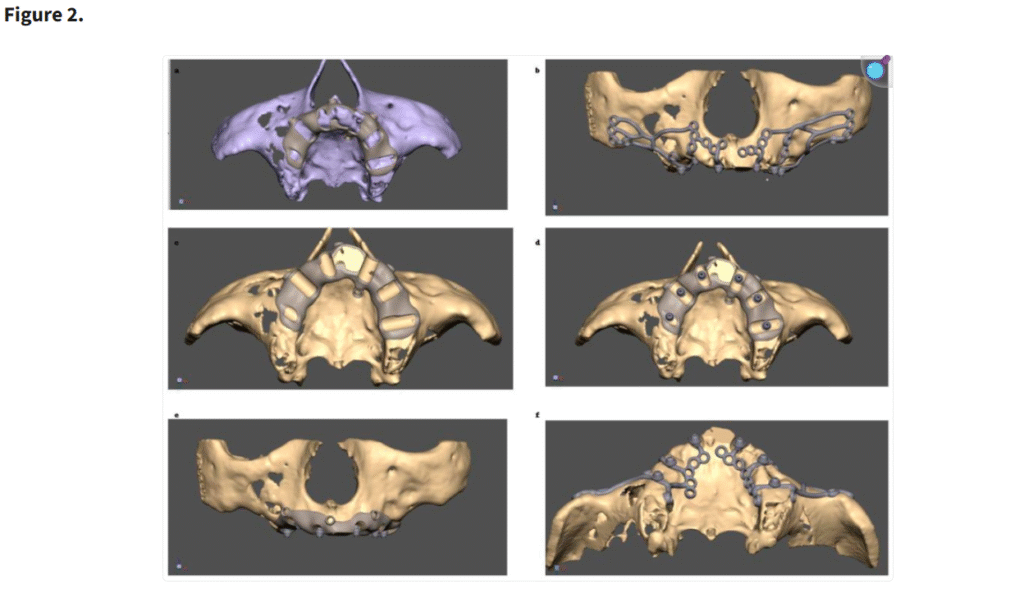

歯槽堤の骨削除用テンプレートの設計プロセス

(a) 骨削除前に歯槽堤にテンプレートを装着

(b, f) 骨上に設置された MaI インプラント®(Integra Implants®, ロッツ〔ポーランド〕)

(c) 骨削除後に歯槽堤にテンプレートを装着

(d, e) 骨削除後の骨上に設置されたマルチユニット

テンプレートの臨床応用(a–d)と、骨整形後の MaI インプラント®(Integra Implants®, ロッツ〔ポーランド〕)の埋入(e, f)